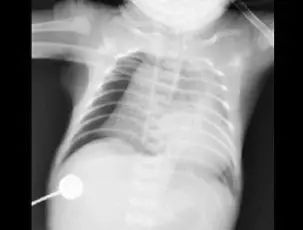

近日,成都1岁多的女孩豆豆(化名)经四川省妇幼保健院急诊科绿色通道快速进入重症医学科抢救。一天前还是活蹦乱跳的孩子,突然被送进重症监护室,而更令所有人大吃一惊的是,胸片显示,孩子的左肺竟然“不见了”?!

7月29日,原本身体很好的豆豆,不知为什么总会连续咳嗽,甚至嗓子都出现了沙哑,还突然出现哮喘,气促、呼吸困难等症状。在医院做完检查后,而胸片的结果却让在场所有人震惊:孩子的左肺竟然“不见了”?!

肺从片子上消失,医学上称为“白肺”。正常的肺部有空气进入,在 CT片上是呈影的。“白肺”,即肺部显影呈一大片的白色状,起因一般是重症肺炎或者大量的胸腔积液。但是豆豆并没有肺部疾病史,究竟是什么原因呢?